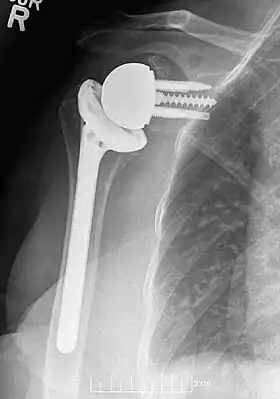

Plain film radiograph in anteroposterior (AP) view of a right shoulder status post reverse shoulder arthroplasty using a prosthesis with a lateralized center of rotation.

Modern reverse shoulder implants consist of multiple parts. On the scapula bone, there is a metallic baseplate that grows into the bone of the native glenoid, screws and/or pegs that hold this in place, and a round metallic “glenosphere” component that is mated to the baseplate via several different mechanisms. On the humerus bone, there is typically a concave polyethylene liner that articulates with the convex glenosphere and is attached to a humeral stem that grows into the native humerus or is cemented into place. Within this basic structure there are multiple different variations of implants, and to date there is no consensus on which design is superior, although several studies have demonstrated some benefits to certain combinations.[9][10][11]